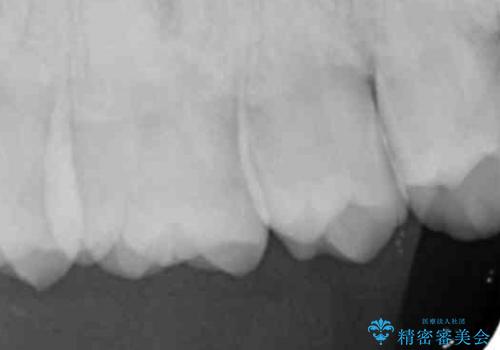

歯と歯の間の虫歯 セラミックインレーでの治療

歯と歯の間に虫歯があったためセラミックインレーで治療をしていきました。

- 右上6 セラミックインレー 77,000円費用は治療当時の料金となります

歯と歯の間は虫歯の好発部位となっています。

今後の虫歯リスクを抑えるためにも適合の良い補綴物を装着することは有効です。